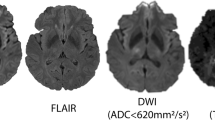

For patients with MCA-territory stroke investigated with MRI, acute diffusion-weighted imaging (DWI) lesion volume has been used to predict neurological deterioration from cerebral oedema. Acute DWI volume of > 80 ml on MRI acquired within 6 h of stroke onset and > 145 ml when imaged 14 h from stroke onset has been shown to predict rapid early neurological deterioration and a need for neurosurgery [52, 53]. However, post-reperfusion DWI often demonstrates temporary diffusion lesion reversal. The apparent diffusion coefficient recovers temporarily so the standard threshold of < 620 × 10−6 mm2/s may not segment the entire visually evident lesion and in some cases the lesion is also not visible on the B1000 image [54]. Decompressive craniectomy performed within 48 h of stroke onset for patients 60 years old or younger reduces mortality by 50% and 72% of survivors post-hemicraniectomy achieve minimal to moderate disability [55••].